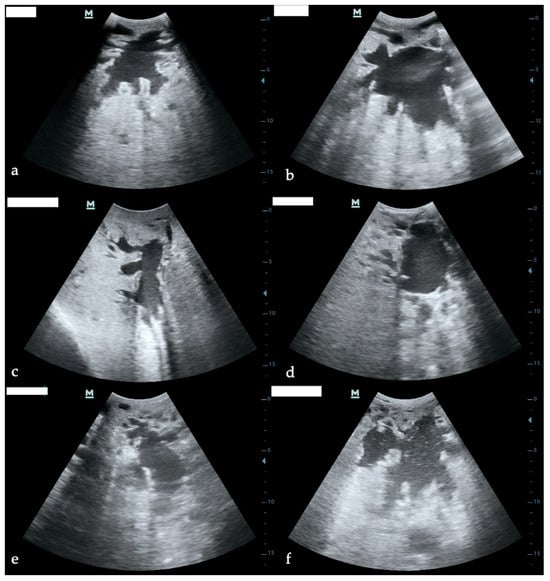

Ultrasonographic Assessment of Glandular Cistern Area in Dairy Cows with Clinical and Subclinical Mastitis: Feasibility, Reliability, and Diagnostic Implications

Ultrasonography has been proposed as a complementary tool for the evaluation of udder health, yet limited information exists on its application for measuring the glandular cistern area during mastitis. This study aimed to investigate modifications of the glandular cistern area in clinical (CM)

Ultrasonography has been proposed as a complementary tool for the evaluation of udder health, yet limited information exists on its application for measuring the glandular cistern area during mastitis. This study aimed to investigate modifications of the glandular cistern area in clinical (CM) and subclinical mastitis (SCM) compared with contralateral healthy quarters, and to assess the reliability of manual and automated ultrasonographic measurements. A longitudinal study was conducted on 42 Italian Holstein cows, comprising 26 SCM and 16 CM quarters, each paired with contralateral healthy controls. Ultrasound examinations were performed at diagnosis (T0), 24 h (T1), and 5 days (T5). Cisternal areas were measured in transversal and longitudinal sections using both manual and ImageJ-guided methods. Intra- and inter-operator reliability was assessed using Intraclass Correlation Coefficients (ICCs). Statistical analyses included two-way mixed ANOVA with post-hoc Bonferroni correction. Mastitic quarters tended to show smaller cisternal areas compared with contralateral healthy quarters, with significant differences observed between contralateral healthy and CM quarters (p < 0.05), but not between contralateral healthy and SCM or between SCM and CM quarters. Temporal trends differed significantly among groups (interaction effect, p < 0.05). Both manual and automated measurements demonstrated excellent intra- and inter-operator reliability, with ICCs consistently > 0.95 across pathology groups and time points. Ultrasonography of the glandular cistern is a feasible, reproducible, and reliable method under field conditions. Clinical mastitis is associated with a measurable reduction in cisternal area, while changes in subclinical mastitis appear less evident. The high reproducibility of measurements, including automated analysis, supports the use of this technique may contribute to improve the use of ultrasound also for the udder heath.

Figure 1